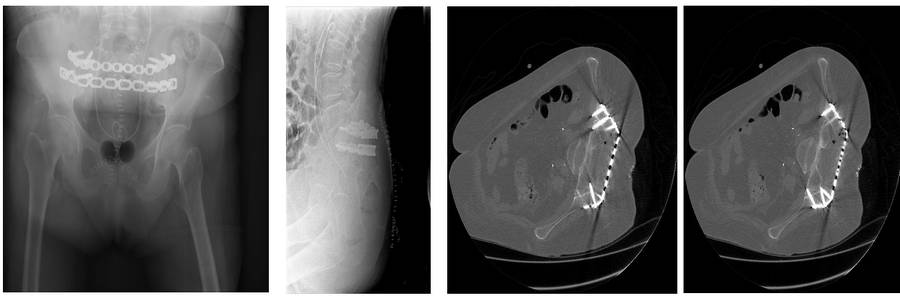

Post-surgery: The titanium plate that was implanted is visible in the X-ray and CT scan.